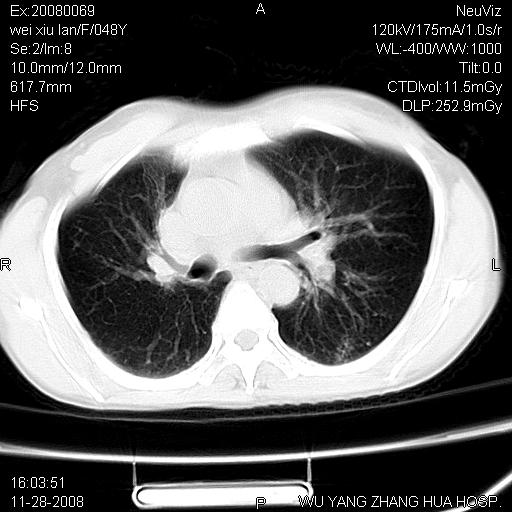

标题: CT16847:女,48岁,咳嗽,发热两日,平常偶有上腹部不适。 [打印本页]

标题: CT16847:女,48岁,咳嗽,发热两日,平常偶有上腹部不适。

能否考虑食管裂孔疝?请老师们多多指教。

支持食管裂孔疝

考虑左侧隔膨升

这个是左侧膈膨升伴不完全性胃翻转,手术将松弛的左横膈膜折叠缝合即解决问题。

支持左侧膈疝,心脏受压右移.

左下肺不张、膈膨升,胸腔胃

1.左侧隔膨升

2.左下肺炎性改变

胃、脾脏及部分肠管明显升高,并压迫心脏移位,

首先考虑:左侧膈疝。

左侧胸腔内见胃肠及脾脏影

支持膈疝

左膈顶及肋膈角均上移,膈面光滑,考虑左膈肌麻痹